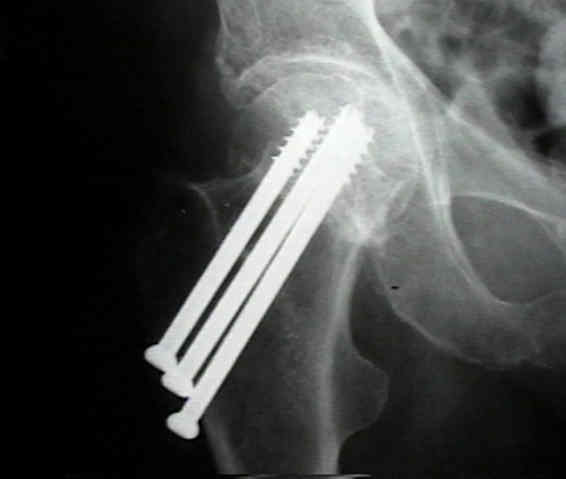

Cannulated Titanium Alloy Bone locking Screws Headed Compression Screw Orthopedic Cortex Bone Screw

| Product name | Cannulated single head compression screws |

| Specification | 4.0x30-60mm with 2mm difference |

| 4.5x30-60mm with 2mm difference | |

| 7.3x60-110mm with 5mm difference | |

| Material | Titanium |

| Related instrument | Instrument set for 4.0/4.5/7.3mm cannulated screws |

| Surface Finished | Oxidation/Milling for Titanium |

| Remark | Customized service is available |

| Fracture | Being good at femoral neck fracture, promoting bone healing faster |